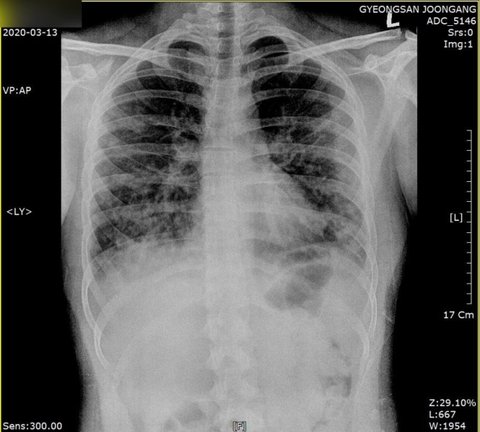

지난 13일부터 사망 당일인 18일까지 매일 찍은 엑스레이 사진은 점차 흰색으로 도배돼 일반인 눈으로도 폐가 제 기능을 할 수 없는 상황임을 알아챌 수 있다.

진료기록과 폐CT·엑스레이를 확인한 대구지역 내과 전문의 A씨는 "엑스레이상 초반에는 오른쪽 폐 상태가 나빴는데 점점 증상이 양쪽으로 심해졌다"며 "처음 방문한 병원에서 침윤 증세, 즉 폐렴 소견을 낸 것으로 보아 첫 번째 병원에 방문하기 전부터 몸 상태가 좋지 않았을 수도 있다는 생각이 든다"고 말했다.